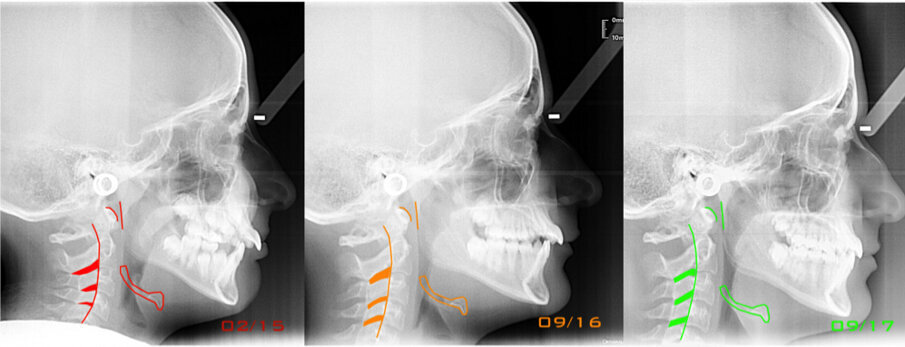

Caso 1 Paziente di anni 9,5, II Classe scheletrica, retrusione mandibolare, contrazione dell’arcata superiore, Overjet elevato (9,5 mm), compressione delle vertebre cervicali. La paziente riferisce di soffrire di cefalee continue. Dall’esame della panoramica e della teleradiografia evince una grande discrepanza tra il condilo dx e sx ed un evidente riduzione dello spazio intervertebrale in corrispondenza delle prime vertebre cervicali. La paziente è sottoposta a terapia elastodontica con AMCOP di seconda classe SC 3 con lo scopo di favorire l’espansione dell’arcata superiore e l’avanzamento mandibolare. A distanza di un anno evince un miglioramento dell’articolazione temporo-mandibolare di sx ed un aumento dello spazio intervertebrale legato a l’avanzamento mandibolare, è evidente inoltre il miglioramento dell’overbite ed overjet. A distanza di 2 anni si assiste ad un netto miglioramento dei condili grazie all’azione scheletrica dell’AMCOP ed a un netto vantaggio posturale con aumento dello spazio tra le vertebre cervicali. La malocclusione si può dire risolta anche se necessita una stabilizzazione del caso clinico attraverso lo stesso dispositivo (Figg. 2-14).

Il caso clinico dimostra come la malocclusione scheletrica avesse delle forti ripercussioni sulla postura e come risolvendo la malocclusione scheletrica si ha anche un ottimo equilibrio posturale come evince dalle teleradiografie.